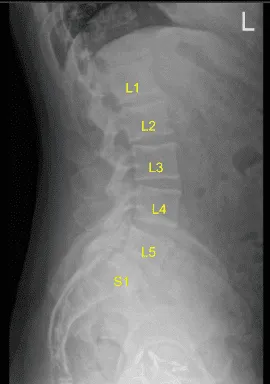

This Patient presented to our outpatient clinic with signs and symptoms of lumbar stenosis and spondylotic radiculopathy as well as epidural lipomatosis. They failed extensively with non surgical treatments, which were unsuccessful in alleviating their symptoms. Imaging demonstrated the above mentioned issue.

Spinal needle and fluoroscopy were used to localize the L5-S1 level. A midline incision was demarcated. Skin was sterilized with DuraPrep. Sterile drapes were placed in usual manner. 1% lidocaine with epinephrine was infused.

Skin was opened with #10 blade scalpel. Hemostasis was obtained with bipolar. Bovie monopolar and Cobb elevators were used to carry the incision down, incising the fascia and performing subperiosteal dissection exposing the L4, L5 and S1. Self-retaining retractors were placed. A Woodson elevator was placed under the L4 lamina. C-arm unit, which was draped sterilely, was brought into the field and used to confirm the level.